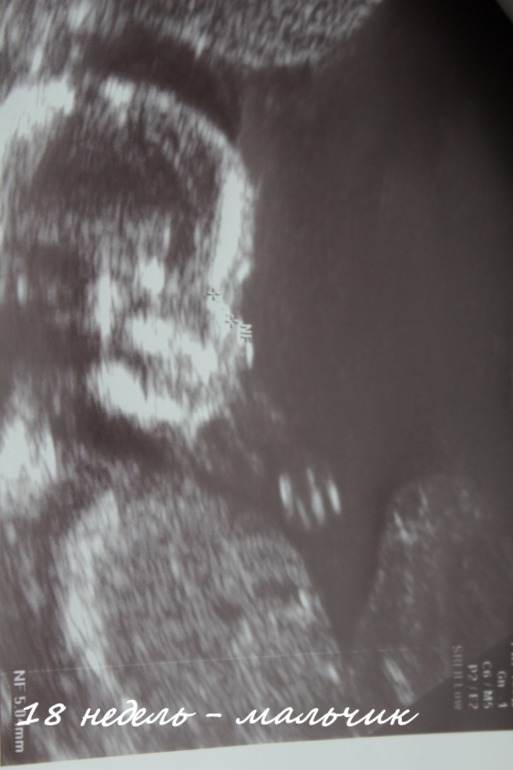

И наша тайна пола раскрыта, у нас будет СЫНОЧЕК!!! Мы очень очень рады!!!

Вот кто в пузике сидит)))